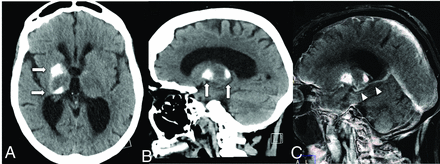

Basal ganglia and deep cerebellar nuclei are regions of the brain with higher metabolic demands. The presence of a DVA in these locations across time may lead to increased mineralization within the affected deep gray matter structure (Fig 4).20 Metabolic abnormalities can also be encountered in the venous drainage territory of a DVA. A small case series of 22 patients found that 76% of DVAs studied had metabolic changes on FDG-PET/CT scans in the form of hypometabolism, which was significantly more common in older patients (Fig 5).21 A subsequent larger study with 54 patients with 57 DVAs showed evidence of metabolic abnormalities in 38% of patients; in this study, hypometabolism was more common in DVAs draining gray matter rather than white matter.22 Hypometabolism has been reported in regions corresponding to neurologic symptoms; for example, hypometabolism was seen in the visual tracts in patients with visual symptoms and a corresponding DVA.23 Most interesting, structural abnormalities (ie, WMH) were not seen in these patients with abnormalities on functional images.21,22 Again, this finding is supportive of the notion that DVAs have a less robust venous drainage pathway.

Noncontrast CT of the head (A and B) shows dystrophic calcification of the anterior right putamen and pulvinar of the thalamus (arrows). CTV MIP sagittal image (C) shows a right basal ganglia DVA (arrowheads) with the collector vein draining into the ipsilateral internal cerebral vein (arrows).